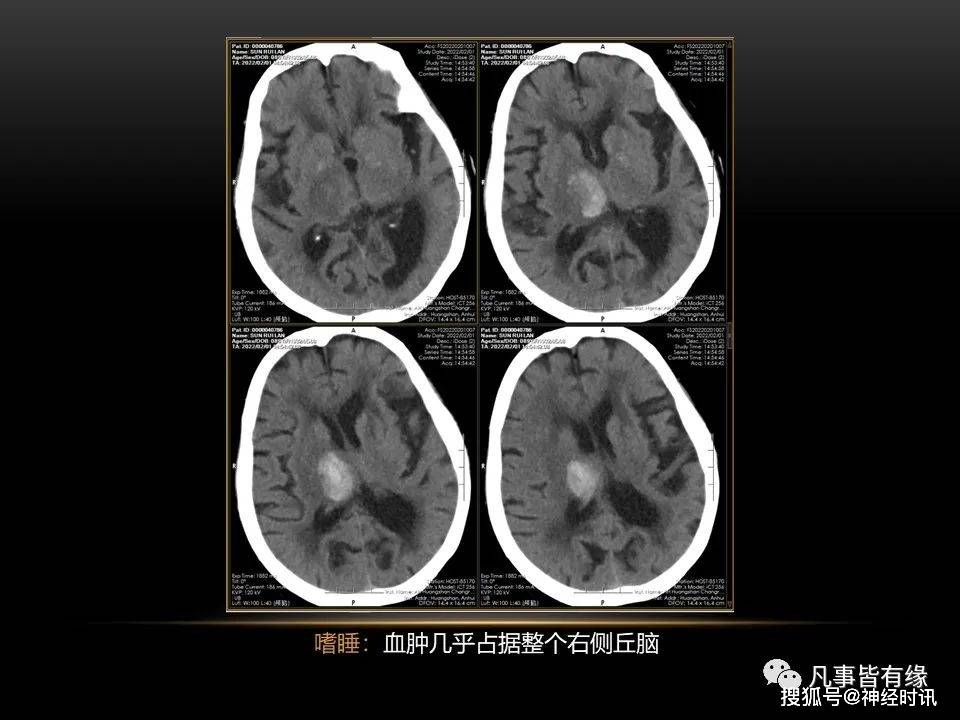

不同部位脑出血截然不同的预后分享交流

高血压性脑出血 临床表现视出血部位,出血量,全身情况等因素而不同.